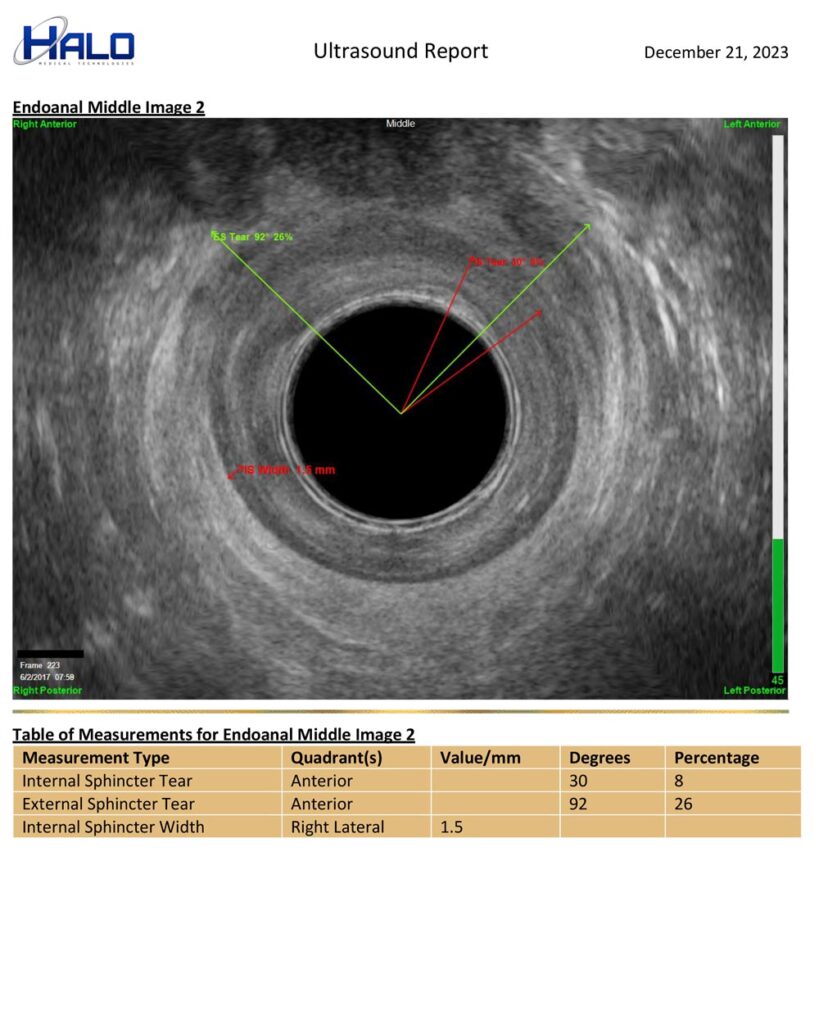

EZ-Reporter Auto-Generated Ultrasound Reports

Perform exams, mark/measure images, & document your interpretation. EZ-Reporter does the rest. The final report is auto-populated with your findings and ready for your patient’s medical record or to be sent to a referring clinician.

Sample Report